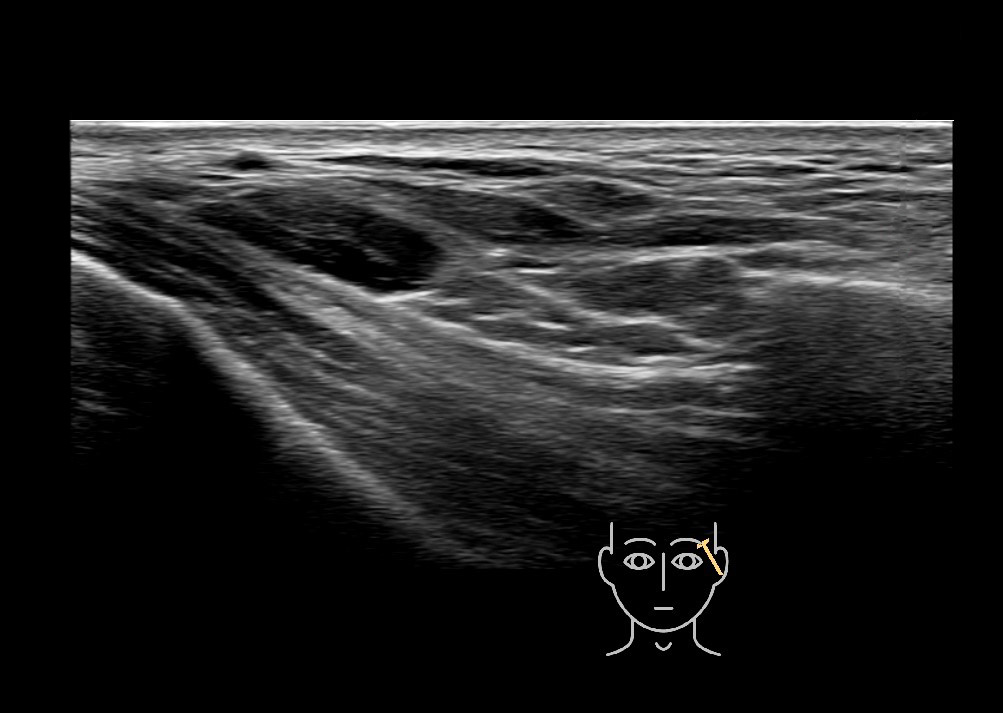

Filler behavior - Temple zygoma US

Study the first image to recognize the different layers. If you are sure about the layers, swipe to the second image to view the answer (if applicable).